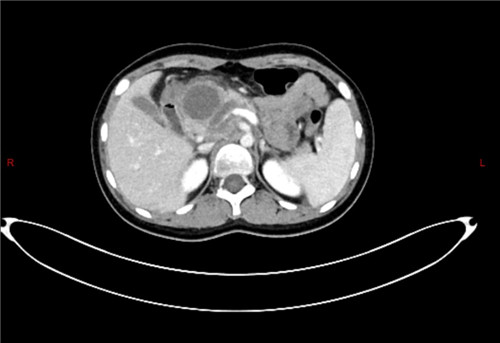

为确保手术安全,医院组织普外科、麻醉科、影像科、重症医学科等多学科专家联合会诊,制定个性化手术方案。术前腹部核磁共振及CT检查提供了肿瘤的位置、解剖关系影像学指导、术中采用先进的高清腹腔镜系统,实现了肿瘤的精准定位和完整切除,展现了医院在儿童疑难疾病综合诊疗方面的强大实力。